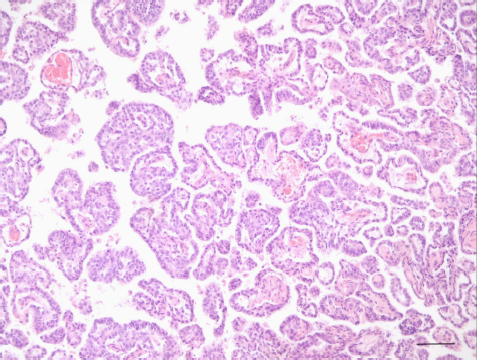

The necropsy revealed the presence of a voluminous dark red irregular mass which from the tympanic bulla invaded the posterior cranial fossa following the left glossopharyngeal nerve through the jugular foramen and the tympanic-occipital fissure (Fig. 2).

Fig. 2. A voluminous dark red irregular mass following the left glossopharyngeal nerve through the jugular foramen and the tympanic-occipital fissure.